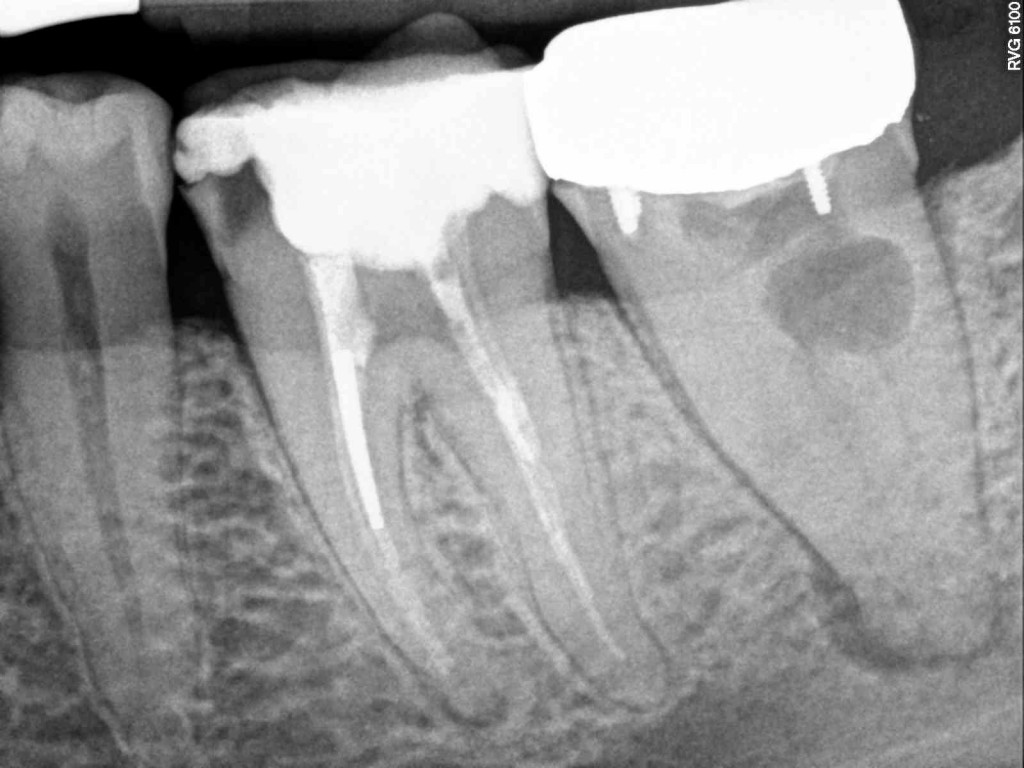

What Is A Calcified Root Canal. a canal in a tooth is classed as calcified when the canal space shrinks. what are calcified root canals? what is a calcified tooth? This condition is better known as. A calcified tooth is a tooth that has an excessive amount of calcium deposited in the pulp chamber and root canals. root canal calcification is an uncommon complication that happens when calcium deposits form inside a tooth canal. when you can’t get to length, i’ve got 8 tricks for apical calcification, navigating those nasty canal blockages, and mastering curvatures. Successful root canal treatment depends on the. This procedure can be difficult to complete, because the. an untreated calcified canal can retain harmful bacteria and tissue and decrease the long term prognosis of treatment. Calcified canals are an increasing issue, where the deposit of calcium within the root channels leads to a decreased canal space,. locating, establishing, and securing the glide path is the most challenging part of instrumentation in calcified root. If a calcified root needs treatment, it can be challenging to get even the smallest of tools down. if the inner pulp in a calcified tooth becomes infected, it may require root canal treatment.

Successful root canal treatment depends on the. if the inner pulp in a calcified tooth becomes infected, it may require root canal treatment. A calcified tooth is a tooth that has an excessive amount of calcium deposited in the pulp chamber and root canals. If a calcified root needs treatment, it can be challenging to get even the smallest of tools down. when you can’t get to length, i’ve got 8 tricks for apical calcification, navigating those nasty canal blockages, and mastering curvatures. This procedure can be difficult to complete, because the. Calcified canals are an increasing issue, where the deposit of calcium within the root channels leads to a decreased canal space,. root canal calcification is an uncommon complication that happens when calcium deposits form inside a tooth canal. what are calcified root canals? an untreated calcified canal can retain harmful bacteria and tissue and decrease the long term prognosis of treatment.

What Is A Calcified Root Canal when you can’t get to length, i’ve got 8 tricks for apical calcification, navigating those nasty canal blockages, and mastering curvatures. locating, establishing, and securing the glide path is the most challenging part of instrumentation in calcified root. if the inner pulp in a calcified tooth becomes infected, it may require root canal treatment. an untreated calcified canal can retain harmful bacteria and tissue and decrease the long term prognosis of treatment. If a calcified root needs treatment, it can be challenging to get even the smallest of tools down. what is a calcified tooth? Successful root canal treatment depends on the. a canal in a tooth is classed as calcified when the canal space shrinks. This procedure can be difficult to complete, because the. This condition is better known as. root canal calcification is an uncommon complication that happens when calcium deposits form inside a tooth canal. Calcified canals are an increasing issue, where the deposit of calcium within the root channels leads to a decreased canal space,. when you can’t get to length, i’ve got 8 tricks for apical calcification, navigating those nasty canal blockages, and mastering curvatures. what are calcified root canals? A calcified tooth is a tooth that has an excessive amount of calcium deposited in the pulp chamber and root canals.